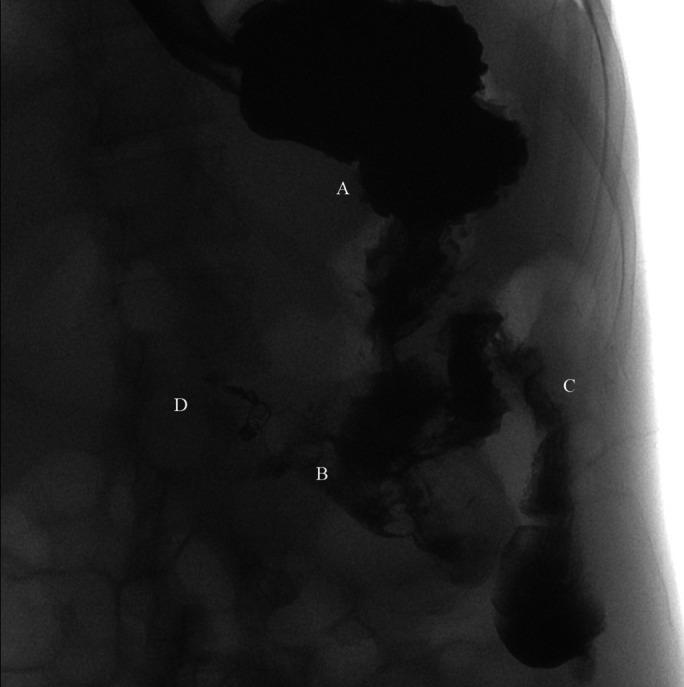

We present a case of a pregnant woman admitted for malnutrition secondary to a large gastrocolic fistula (GCF). She has a history of perforated duodenal ulcer that required surgical pyloroplasty 6 years ago. This fistula was diagnosed on the gastrointestinal barium series showing direct transit of barium from the stomach to the colon. An upper endoscopy showed a large gastrocolonic fistula with stool leaking to the stomach. Her nutrition was optimized, then she underwent surgical repair. GCF is suspected in the patient presenting with malnutrition with a history of intra-abdominal surgery.

我们报告一例因巨大胃结肠瘘(GCF)继发营养不良而入院的孕妇。她有十二指肠溃疡穿孔病史,6年前接受了手术幽门成形术。该瘘在胃肠道钡剂造影检查中被诊断出来,显示钡剂从胃直接进入结肠。上消化道内镜检查显示一个巨大的胃结肠瘘,粪便漏入胃内。对她的营养状况进行了优化,然后她接受了手术修复。对于有腹部手术史且出现营养不良的患者,应怀疑存在胃结肠瘘。